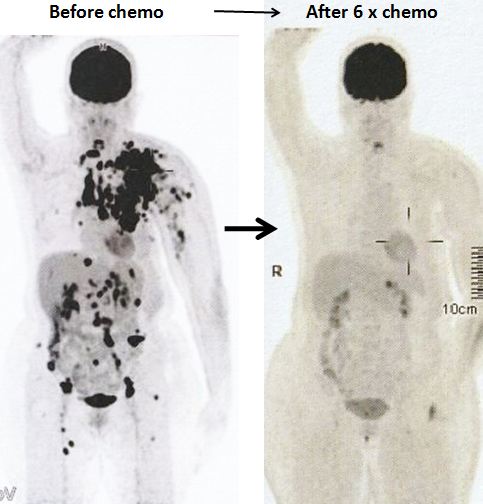

8. Pemindaian PET pada 14 April 2022 memang menunjukkan respon yang baik.

Sebelum kemo ———– setelah 6 siklus kemo

1. Temuan scan menunjukkan respon metabolik lengkap pada kekambuhan dinding dada, metastasis nodal dan penyebaran jauh.

2. Perubahan atelektasis baru pada dasar paru kiri dengan efusi pleura kiri ringan mungkin disebabkan oleh infeksi baru-baru ini.

1. Hasil kemoterapi yang luar biasa.

Bandingkan ketiga gambar ini :

Kiri: Setelah operasi Lucy menjalani terapi alternatif, menolak kemoterapi. Hasilnya adalah metastasis luas (tengah).

Kanan: Lucy tidak punya pilihan selain menjalani kemoterapi. Hasil dari 6 siklus kemoterapi sungguh luar biasa! Selama lebih dari 25 tahun saya berurusan dengan pasien kanker, saya belum pernah melihat hasil kemoterapi yang luar biasa seperti ini. Salut dengan ahli onkologi! Anda menyelamatkan Lucy!

Faktanya, hasil chemo ini sangat sulit dipercaya sehingga orang tergoda untuk bertanya apakah itu asli dan bukan palsu? Jawaban saya TIDAK, studi detail hasil PET scan di bawah ini adalah nyata! Kaji gambar berikut dengan cermat – sebelum dan sesudah kemoterapi.